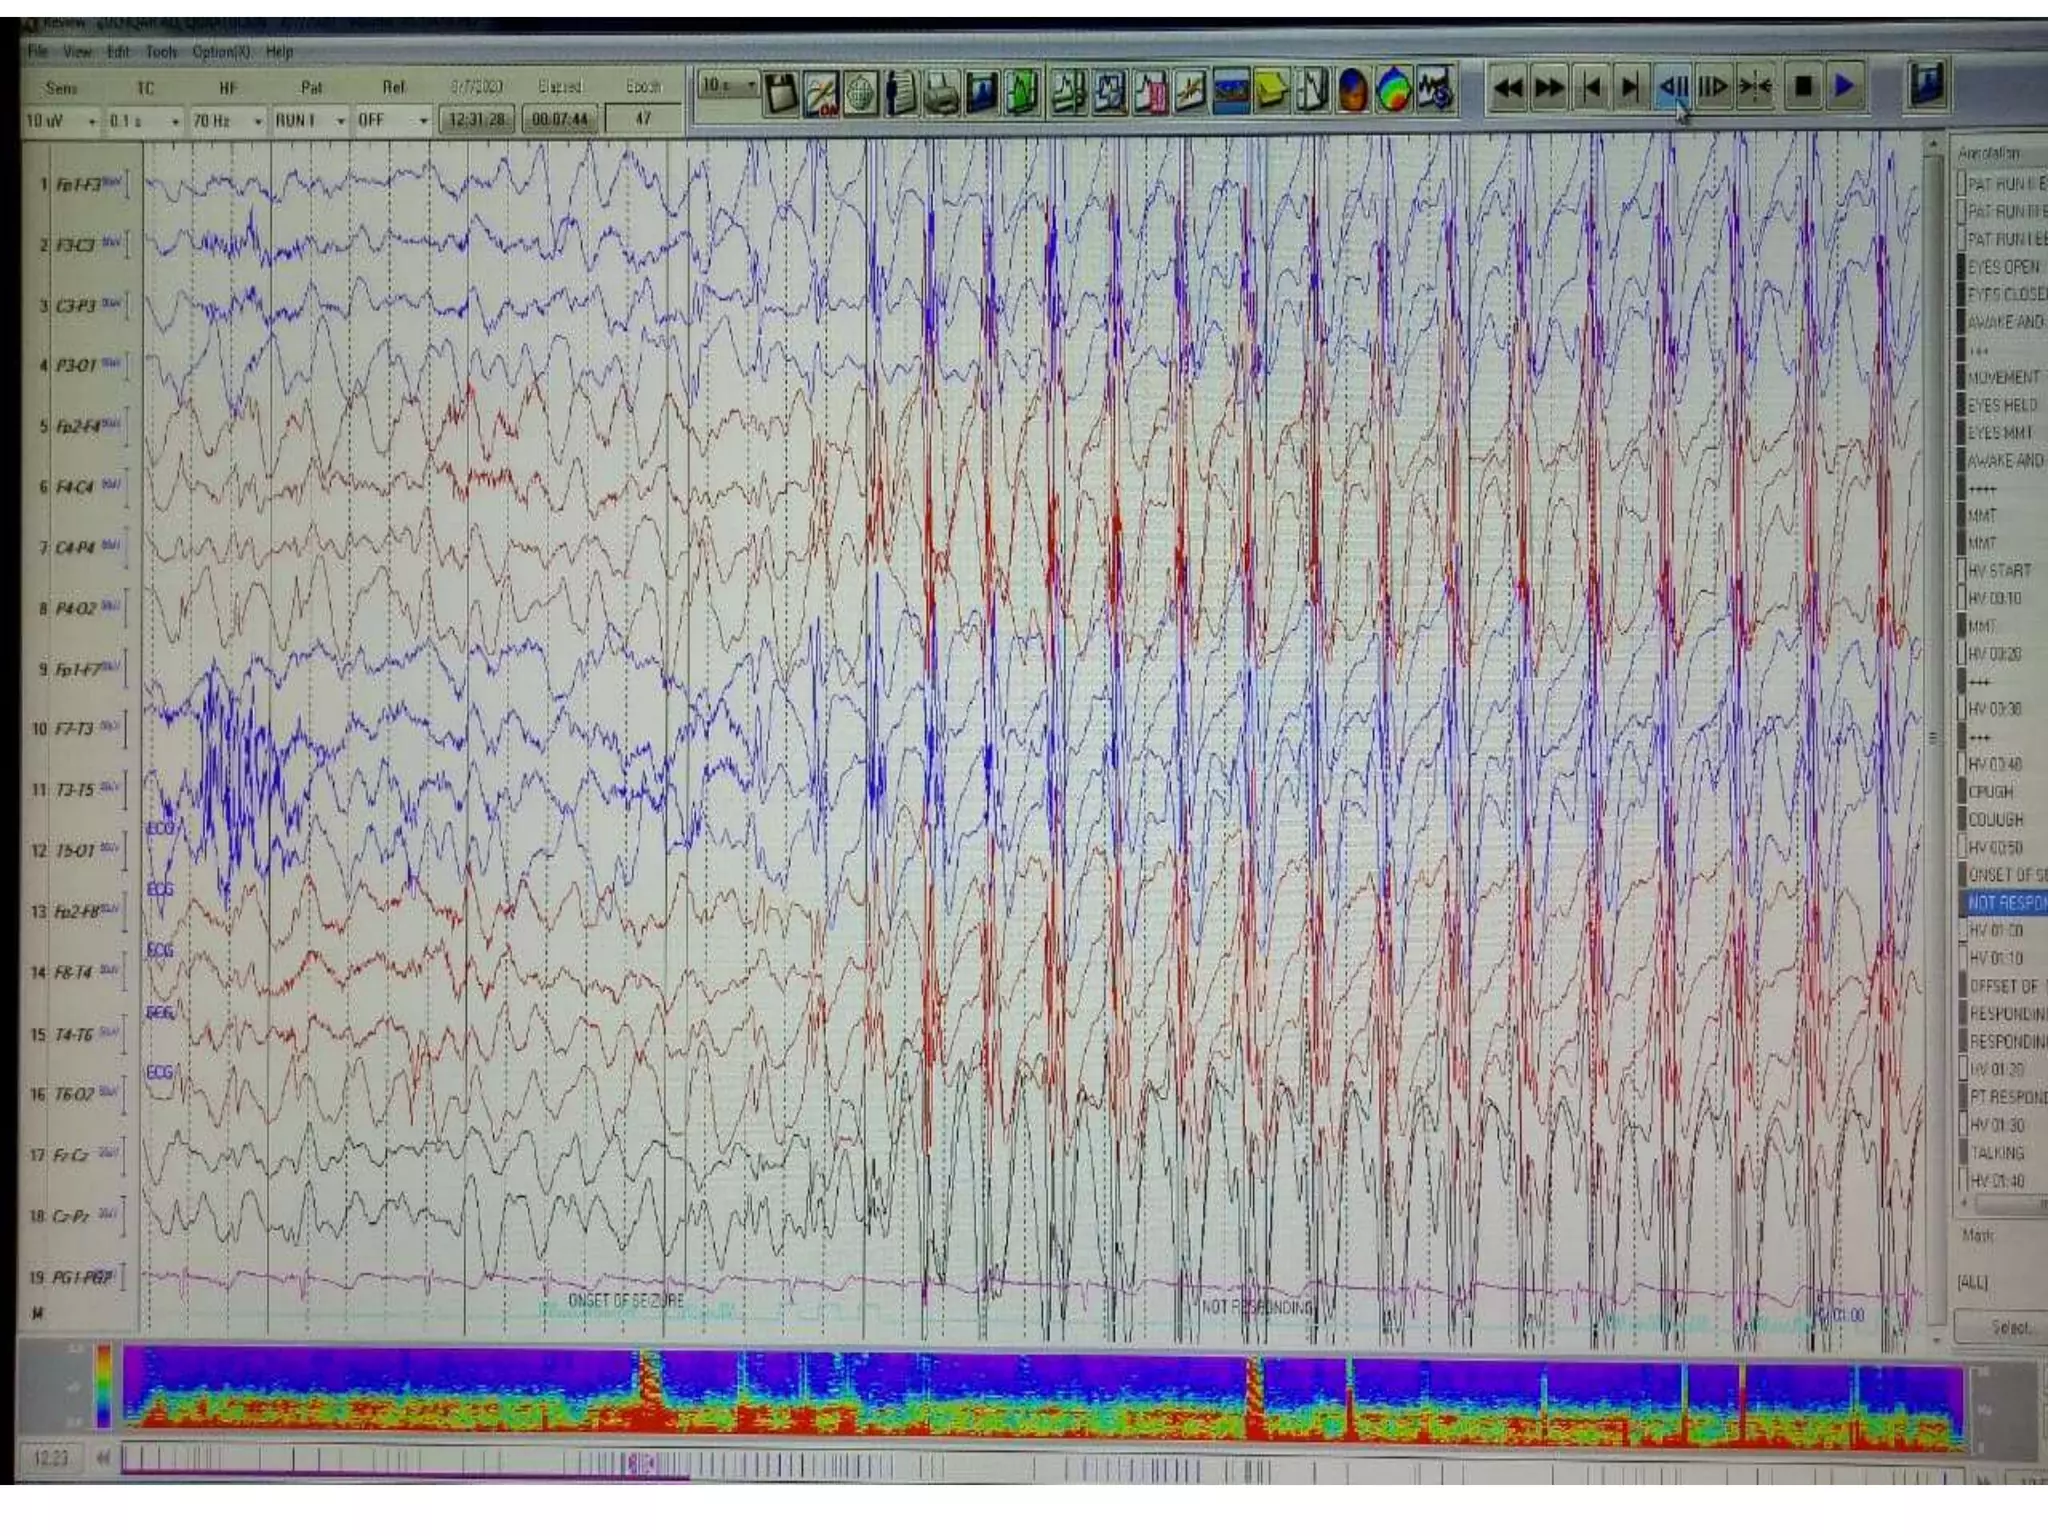

ABSENCE SEIZURES

The three Hz spike and wave pattern is suggestive of

idiopathic Generalized epilepsy.

• Characteristics:

It is classically described with typical absence epilepsies when bursts

of 3Hz spike and wave is Gen, regular, symmetrical, synchronous and

maximal in the anterior head region

Clinical symptoms: fluttering of eyes and automatism.

It usually occurs in patients aged b/w 5-12 years.

Onset : At 2 years and can be appeared till 14 years.

• Often faster at onset and slows down toward end.

• Accentuated (more prominent) by HV (50-80% pt) and photic

stimulation (about 20% of pt).